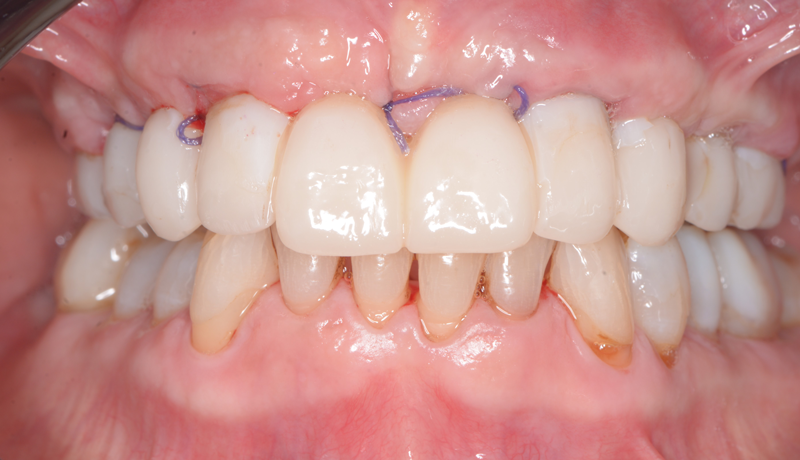

Protesi definitiva posizionata in bocca

Controllo a 2 giorni, si noti ancora il gonfiore del viso

Controllo a 15 giorni